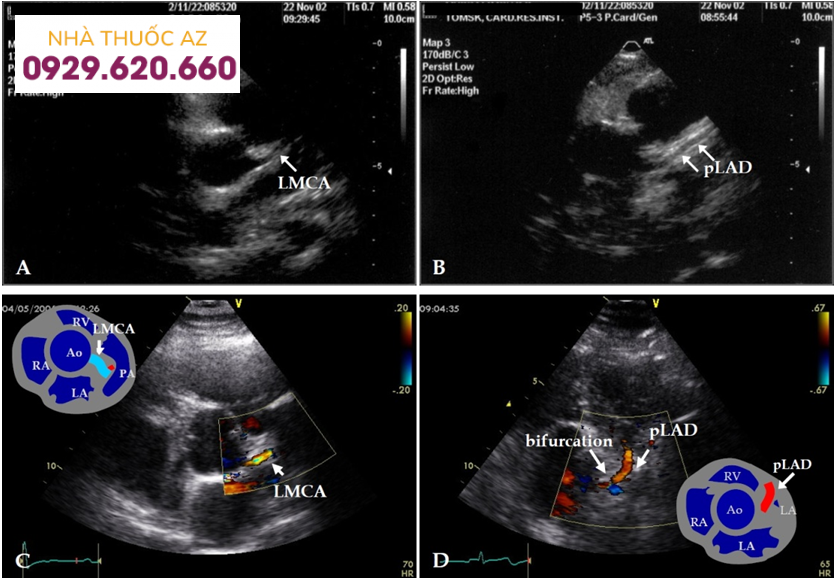

Hình ảnh van động mạch chủ trên siêu âm tim

Siêu âm doppler tim là xét nghiệm lựa chọn để phát hiện và định lượng độ lớn dòng hở-hẹp và mức độ nghiêm trọng tổng thể của hở-hẹp van động mạch chủ. Siêu âm hai chiều có thể khảo sát kích thước gốc động mạch chủ cũng như giải phẫu và chức năng sinh lý của thất trái.